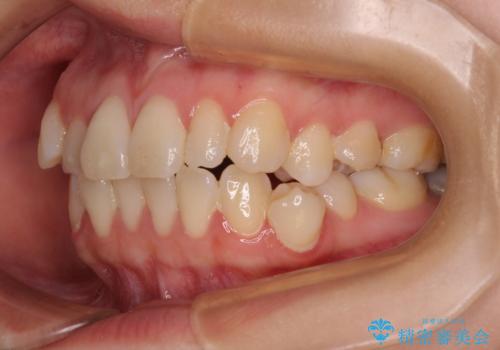

- 20代女性

- 患者様は「歯並び全体のデコボコが気になり、人前で笑うことに抵抗がある」とのことでご来院されました。

診査の結果、上下顎ともに叢生が認められましたが、ワイヤー矯正・マウスピース矯正のいずれでも対応可能な症例でした。